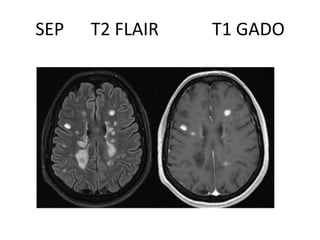

Affection Démyélinisante de la

substance blanche

• Inflammatoire : sclérose en plaques : SEP

• Sclérose en plaques : SEP

– C’est une maladie inflammatoire du SNC ,

d’étiologie inconnue , touchant la femme jeune ,

secondaire à une démyélinisation des fibres

nerveuses du cerveau , de la moelle épinière et des

nerfs crâniens

– IRM: Gold Standard+++ dans le diagnostic + et le

suivi évolutif de cette affection

Les critères diagnostics de la SEP : critères de McDonald:

• IRM: Lésions multiples de taille et de forme variables,

bilatérales et asymétriques de la substance blanche en

iso ou hypo signal T1 , hyper signal T2/FLAIR avec prise

de contraste Gado des plaques récentes.

• Lésions disséminées dans le temps et dans l’espace

• Prédominance à la substance blanche péri ventriculaire

et corps calleux

• Si les lésions sont anciennes : hypo signal T1

• « trou noir » , non rehaussées  lésions séquellaires

SEP

SEP T2 FLAIR T1 GADO

Affection Démyélinisante dela substance blanche • Inflammatoire : sclérose en plaques : SEP • Sclérose en plaques : SEP – C’est une maladie inflammatoire du SNC , d’étiologie inconnue , touchant la femme jeune , secondaire à une démyélinisation des fibres nerveuses du cerveau , de la moelle épinière et des nerfs crâniens – IRM: Gold Standard+++ dans le diagnostic + et le suivi évolutif de cette affection

Les critères diagnosticsde la SEP : critères de McDonald: • IRM: Lésions multiples de taille et de forme variables, bilatérales et asymétriques de la substance blanche en iso ou hypo signal T1 , hyper signal T2/FLAIR avec prise de contraste Gado des plaques récentes. • Lésions disséminées dans le temps et dans l’espace • Prédominance à la substance blanche péri ventriculaire et corps calleux • Si les lésions sont anciennes : hypo signal T1 • « trou noir » , non rehaussées  lésions séquellaires

SEP T2 FLAIRT1 GADO